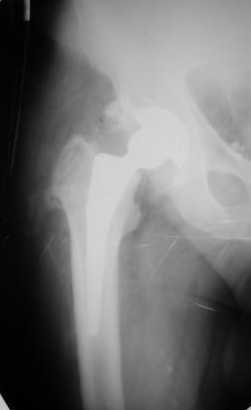

Сегодня свершилась ревизия. С максимально бережным отношением к тканям выделил бедро.

Ножка "слету " удалить не удалось, после выделения долотом ножку удалил.

Поставил Corail большего размера.

Рентгенограммы вывешу.